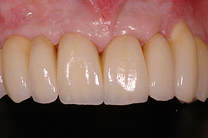

Fallbeispiel

Zum Vergrössern klicken